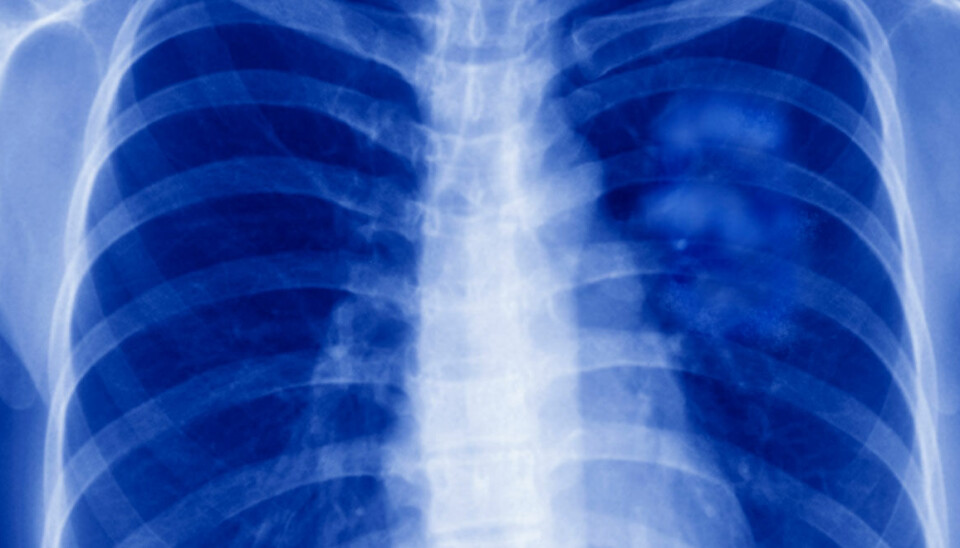

For første gang er en lunge fra en genmodifisert gris transplantert til en hjernedød person.

Lungen fungerte i ni dager før studien ble avsluttet. Det oppsto ikke infeksjoner, men lungen viste tegn til væskeansamling og skader allerede etter ett døgn.

Griselungen ble transplantert til en 39 år gammel mann i byen Guangzhou. Mannen var erklært hjernedød etter en hjerneblødning, og familien hadde godkjent prosedyren.